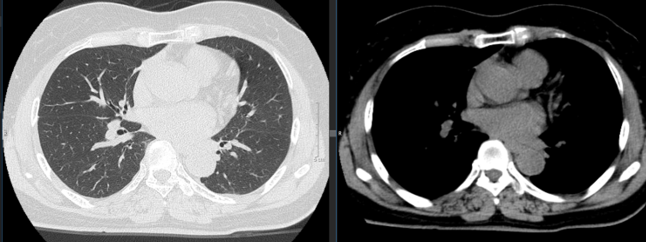

Hình 2:  Hình ảnh chụp cắt lớp vi tính ngực: Không phát hiện các khối, nốt bất thường.

Nhận xét: Sau 4 chu kỳ điều trị Pembrolizumab, không thấy tổn thương ở nhu mô phổi hai bên, hạch ngoại vi không phát hiện cả trên khám lâm sàng và siêu âm.